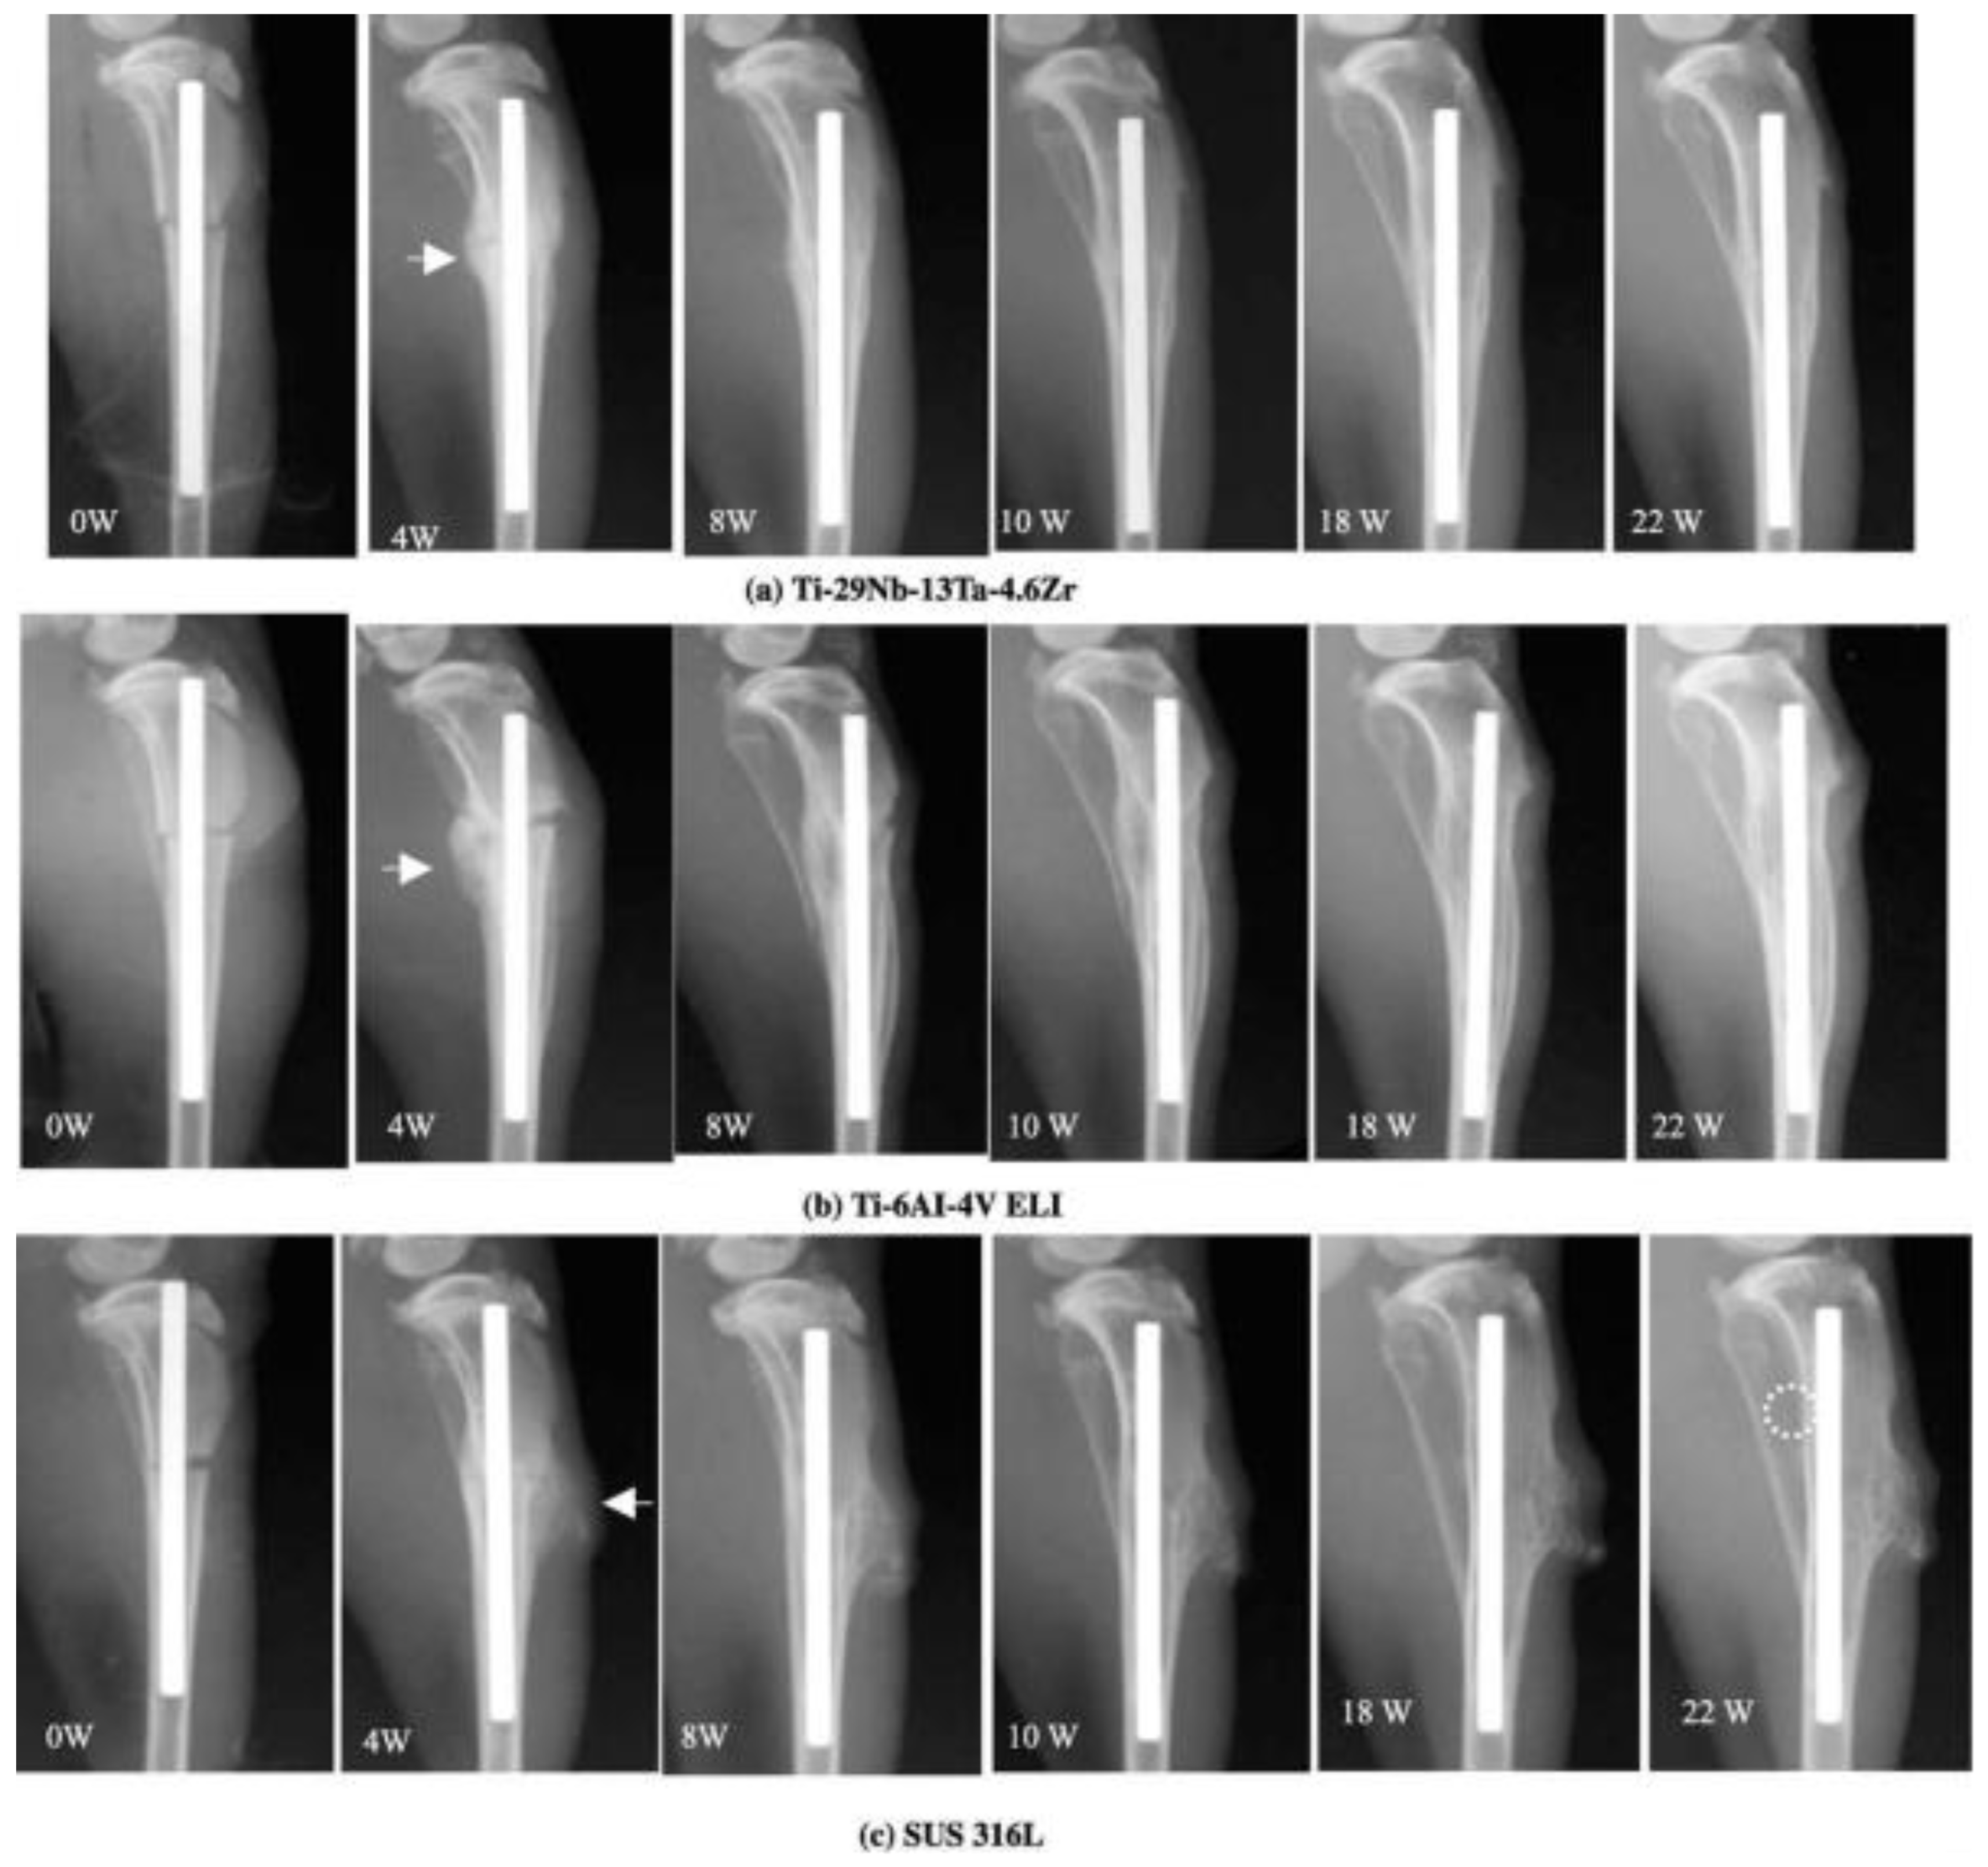

- Hatori, T.; Morikawa, K.; Niwa, S.; Niinomi, M.; Suzuki, A. Bone Tissue Reaction to New b Titanium Low Rigidity Alloy: Rabit Study on Bone Healing Remodeling and Atrophy in Intramedullary Fracture Fixation. In Proceedings of the International Conference on Biomechanics Combined with the Annual Scientific Meeting of Taiwanese Society of Biomechanics, Taipei, Taiwan, 9–11 November 2001. [Google Scholar]

- Hattori, T.; Morikawa, K.; Niwa, S.; Sato, K.; Niinomi, M.; Suzuki, A. Material Rigidity of Fracture Fixation Device and Bone Tissue Reaction—Experimantal Study on Intramedullary Fixation with Different Materials. J. Jpn. Clin. Biomech. 2002, 23, 299–304. [Google Scholar]